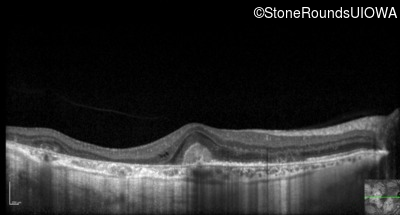

Optical Coherence Tomography - Right - 20/20 -3

Exemplar / OCT Stack

OCT Stack